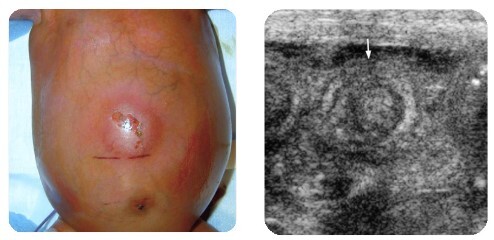

Q

A

Signo de migaja de pan